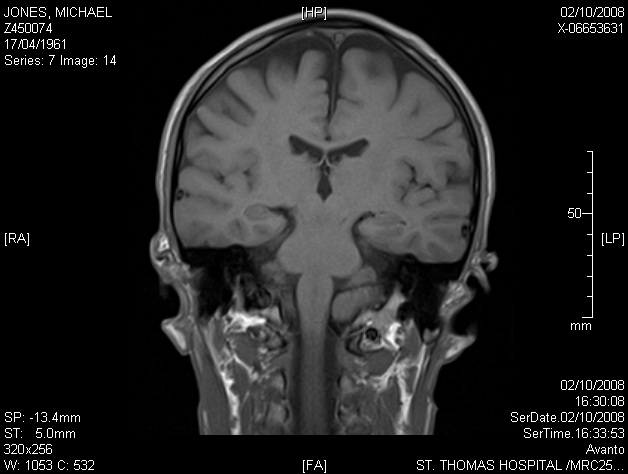

Image 7.14 — in this image, approximately 6mm to the rear of 7.13, the same object appears more clearly defined.

« 7.13 (full)  |  7.14 (detail x4)  |  7.15 (full) »